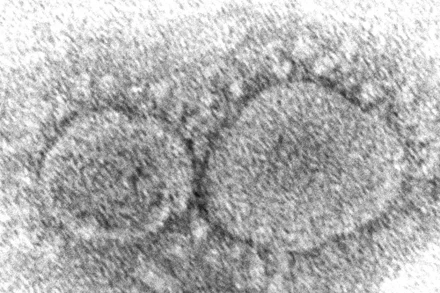

Hình ảnh phần tử virus SARS-CoV-2 gây ra Covid-19 qua kính hiển vi điện tử do Trung tâm Kiểm soát và Phòng ngừa Dịch bệnh Mỹ cung cấp.

Khoa học - Công nghệ